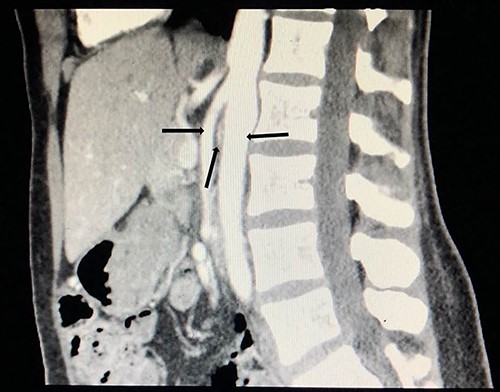

To investigate the bleeding source, she subsequently had a CT renal angiogram 3 days later that showed a narrow angle between origin of SMA and the aorta (Fig. 3) with multifocal areas of hypoattenuation throughout the left renal cortex (Fig. 4). It showed a compression ratio of 3.25 (diameter of pre-compressed vein =6.5 mm; diameter of compressed vein =2 mm) (Fig. 5).

Computed tomography angiogram on presentation, sagittal view showing origin of SMA (left arrow) and the aorta (right arrow) with the compressed LRV in the narrow angle (middle arrow).